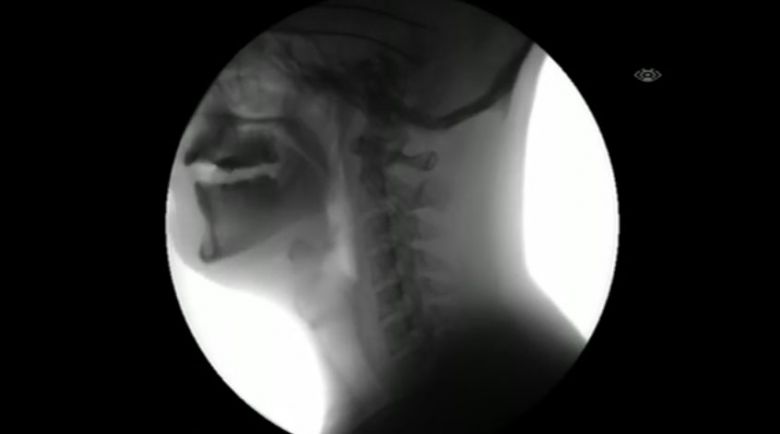

Jak wygląda przełykanie na zdjęciach rentgenowskich (wideo)